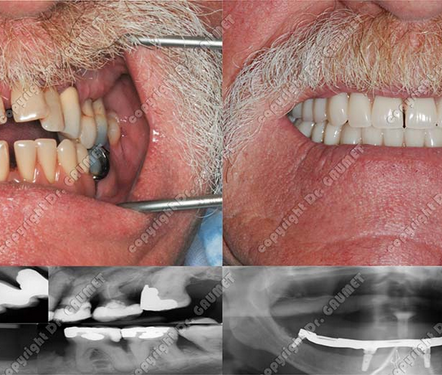

Situé au cœur du Flon à Lausanne, le cabinet du Dr Pierre Gaumet, spécialiste en parodontie et implantologie, est une adresse de confiance pour préserver et restaurer la santé de votre sourire. Fort de plus de 30 ans d’expérience et plus de 3 000 implants posés, le Dr Gaumet allie savoir-faire, sens esthétique et technologie de pointe pour offrir des traitements fiables, durables et confortables. Nous vous accueillons dans une atmosphère chaleureuse et rassurante, où l’écoute et le respect du patient sont au centre de chaque démarche.

Nous proposons une prise en charge complète, allant du traitement de la parodontite et des récessions gingivales, aux implants dentaires, en passant par les greffes osseuses, l’extraction des dents de sagesse et la réhabilitation esthétique du sourire. Grâce à la sédation consciente, même les patients les plus anxieux peuvent recevoir leurs soins en toute sérénité. Cette approche globale permet d’éviter des déplacements entre plusieurs spécialistes et garantit des solutions personnalisées, transparentes et adaptées à chaque situation, avec toujours la solution la moins invasive privilégiée.

- Implantologie dentaire

Remplacement des dents manquantes par des implants fiables et durables pour préserver l’os et le confort de mastication.

- Esthétique du sourire

Relooking du sourire, réhabilitation complète, alignement, harmonisation et soins esthétiques pour un sourire naturel.